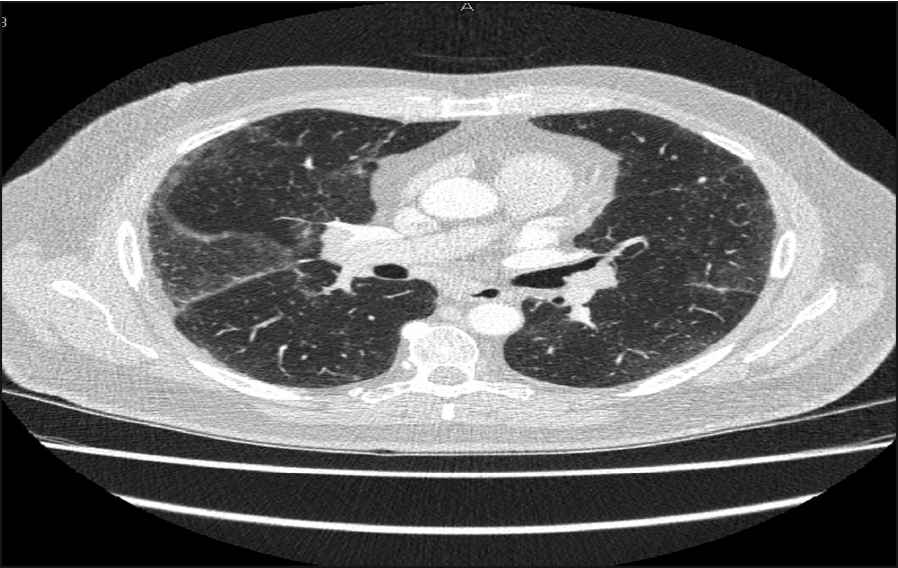

Figure 1. Bilateral lymphadenopathy with left basal infiltrate

Chest x-ray showed bilateral hilar adenopathy with left basal infiltrates (see Figure 1)

His previous chest x-ray dating back to 2004 was normal. CT pulmonary angiogram (CTPA) did not show any pulmonary embolus, however it showed the presence of thoracic and abdominal lymphadenopathy.